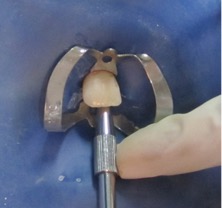

Se presenta el caso de un paciente de sexo femenino, de 8 años de edad. La paciente acudió acompañada con su padre al servicio de endodoncia del Instituto Nacional de Salud del Niño en Lima- Perú, con antecedentes de traumatismo dental, en sector antero superior y con dolor espontáneo. Al examen clínico intraoral, se evaluó que el diente 11 presentaba una ligera movilidad dental y al examen radiográfico se observó diente 11 no vital, ligero ensanchamiento del ligamento periodontal y desarrollo radicular en estadio 8 de Nolla (Figura 1 y 2). Se evaluó el caso y se realizó la explicación de las ventajas y desventajas del tratamiento de revascularización pulpar al padre de familia y se procedió a la firma del consentimiento informado para el tratamiento.

Figura 1: Pza. 11 con antecedentes de traumatismo alveolo dentario.